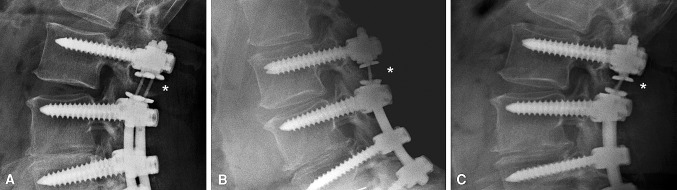

Fig. 2A–C.

(A) A TO implant is shown after removal from a patient requiring surgical revision because of a ruptured titanium alloy cable 26 months after implantation. (B) Lateral and (C) AP radiographs show a representative case of implant failure with breakage (*) and subsequent migration (#) of the cable.

Fig. 3A–C.

Radiographs show representative kinking of the titanium alloy cable (*) in a patient from the TO group. (A) AP translation is visible in the lateral radiograph in neutral position. (B) Despite segmental motion under flexion stress, a lateral radiograph demonstrates an almost fixed retrolisthesis of the implant. (C) Similar retrolisthesis can be observed in a lateral radiograph under extension stress.

In four of the 17 patients of the SL group and six of the 20 patients of the TO group, we observed implant failures, which were all related to breakage of the titanium alloy cable (Fig. 2), with one patient in each group at the 12-month followup and all others at the 24-month followup. The subgroup with implant failure in both groups presented larger direct postoperative implant translation (overall, p < 0.001; SL, p = 0.079; TO, p < 0.001). Furthermore, postoperative posterior disc height was greater for the subgroup of patients with implant failure within the SL group (Table 2). In patients with large implant translation, we unexpectedly observed this translation to be fixed in extension and flexion, regardless of the direction of translation (anterior versus posterior) (Fig. 3). Small implant translations resulted in physiologic motion behavior of the dynamically instrumented level in extension-flexion.